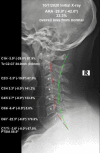

We present the case of a patient receiving structural rehabilitation following a rear-impact motor vehicle collision (MVC). Medications did not alleviate the symptoms of the crash injuries. Resolution of injury-caused pain and disability was found following postural and structural rehabilitation treatment. A 39-year-old male was injured in a rear-impact collision between two very large vehicles. Severe migraine headaches, neck pain, and radiculopathy, as well as lower back pain, were the result of the crash. Patient-reported outcomes (PROs) demonstrated that the symptoms were causing severe disability and poor health-related quality of life (HRQoL) measures. Radiographs found spine alignment abnormalities consistent with rear impact MVC. Chiropractic Biophysics® (CBP®) structural rehabilitation was performed. Following a treatment regimen involving strengthening weakened and damaged muscles, postural and spinal traction, postural spinal manipulative therapy (SMT), and home therapies resulted in the resolution of the symptoms. All outcome measures demonstrated improvement, including Short-Form 36 question health questionnaire (SF-36), quadruple visual analog scale (QVAS), headache disability index (HDI), neck disability index (NDI), revised Oswestry disability index (RODI), as well as significant measured improvements found on radiographs. Spine pain and altered alignment are frequent results of MVCs. If left uncorrected, these abnormalities increase the likelihood of chronic pain and disability. Combined low back pain (LBP), neck pain (NP), headache (HA), and radiculopathy, as found in our subject, significantly pre-dispose the individual to poor HRQoL, years lived with disability (YLDs) and increased the global burden of disease (GBD). Physicians who treat injured patients should have a repeatable, reliable, valid, and efficacious method to reduce pain, increase range of motion (ROM), improve spine alignment, and improve the performance of activities of daily living (ADLs). Further, larger studies of injured patients are necessary to determine if the CBP® protocol reduces GBD caused by MVC injuries.